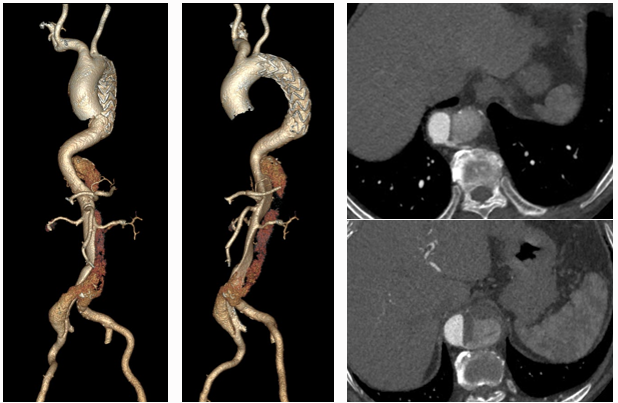

主动脉重塑差异与301分型

★ 术后转归差异

重塑差:假腔持续扩张,真腔受压(图文对照显示术后1年假腔未闭合)

重塑好:真腔恢复血流,假腔血栓化(影像显示术后1年假腔消失)